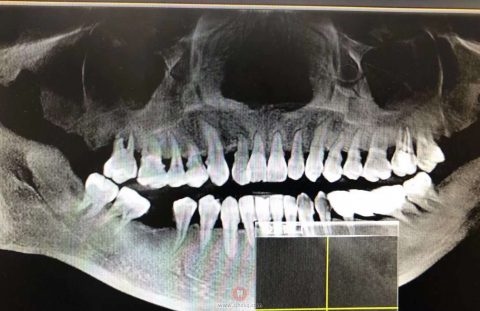

今日有4年前就诊的朋友,有朋友推荐成群结伴而来的牙友;今日还接诊一位早上9点左右外伤的患者:因面部无外伤,上唇一点挫裂伤,去了**院就诊和交警大队,觉得基本没问题,因上门牙稍微松动下午过来杭口城西徐医生团队就诊,经过简单检查和过程了解,徐医生觉得可能有骨折,徐医生特意嘱咐放射医生尽可能拍摄面中部(我院放射医生也非常负责,电话通知我们确认后让患者回诊室),经牙科CT可以明显看出患者面中部鼻梁、眶底、眶内侧壁存在明显折裂线,真是“飞来横祸”,此病例不详细了解病史极其容易遗漏诊断,进而延误治疗,愿大家都平安快乐